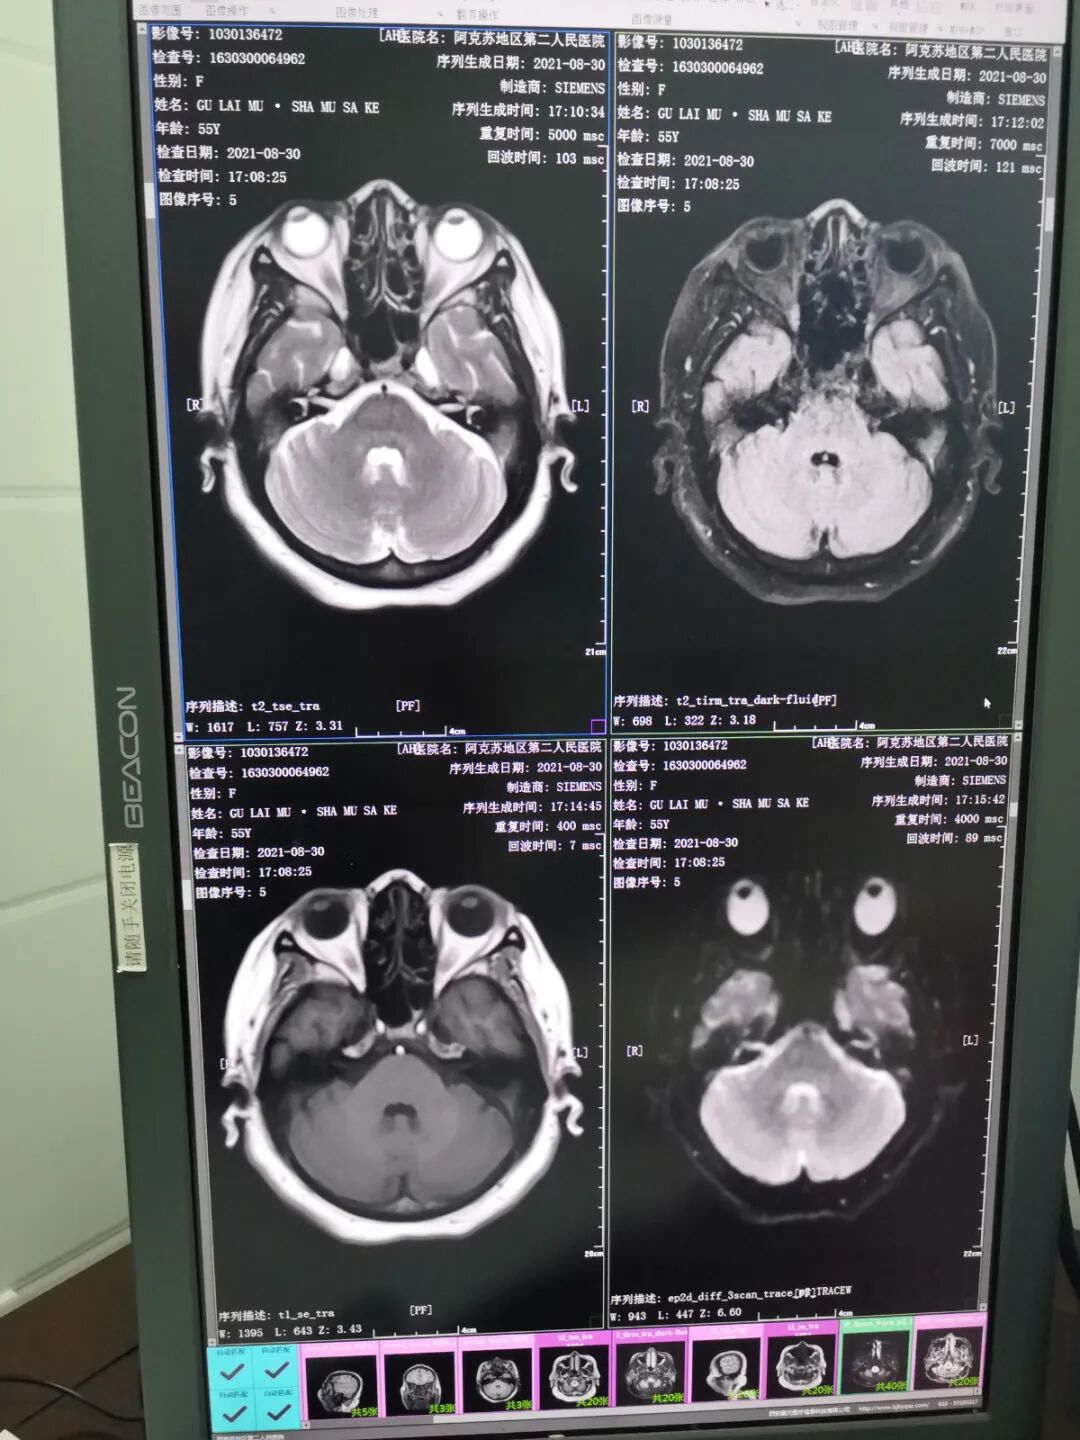

肺部CT图像                                 脑部磁共振图像

CT检查可以多个平面观察组织结构,反映骨骼的立体形态,对肺部疾病、发现细微的骨折、中枢神经系统疾病、头颈部疾病的诊断等有很大帮助。